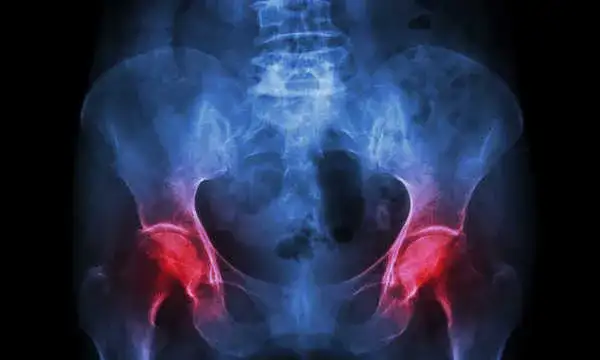

Bonviva to lek stosowany w leczeniu osteoporozy, który ma na celu wzmocnienie kości i zmniejszenie ryzyka złamań. Przed rozpoczęciem terapii ważne jest, aby być świadomym potencjalnych skutków ubocznych, które mogą wystąpić. Wśród najczęściej zgłaszanych efektów ubocznych znajduje się ból stawów, który zazwyczaj ma łagodny charakter, ale może być uciążliwy dla pacjentów.

Wśród najczęstszych skutków ubocznych Bonviva można wymienić ból stawów, który występuje u wielu pacjentów. Objaw ten może być odczuwany jako łagodny dyskomfort, ale w niektórych przypadkach może prowadzić do trudności w poruszaniu się. Inne powszechne efekty uboczne to bóle głowy oraz nudności, które również mogą wpływać na samopoczucie pacjentów.

- Ból stawów: łagodny dyskomfort, który może utrudniać poruszanie się.